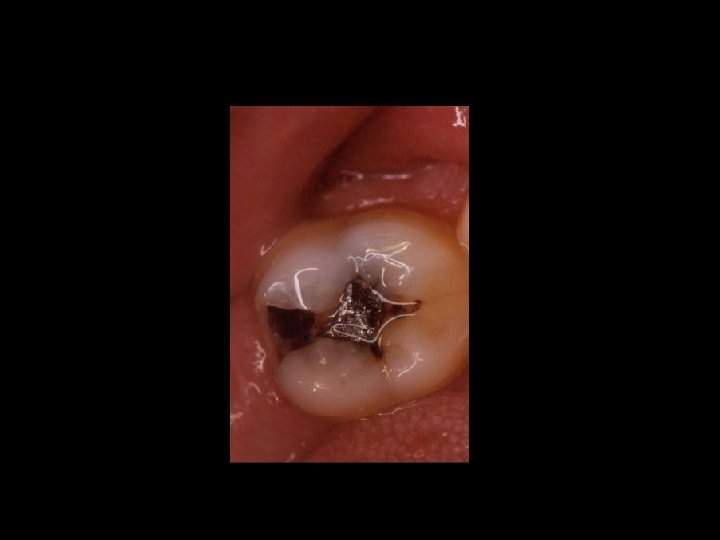

Responsabilità Ø Restauro della corona del dente Ø Trattamenti radicolari